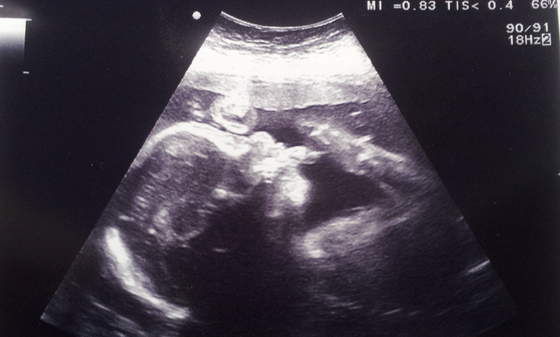

To jest Mateusz drugi do wyjscia z kciukiem w buzi

20120922_160614.jpg

A to Filip z mamusinym noskiem, biedactwo ladniutkie po mamusi ale brzydki profil tez po mamusi, nie bedziemy mu robic zdjec profilu :PPP